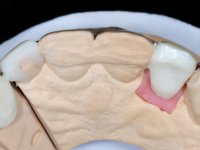

Treatment began with re-preparation of the cast post and core, with the purpose of placing the cervical finishing lines with an intra-sulcular location and simultaneously making a suitable temporary crown. With a very simple orthodontic treatment, the diastema was closed between the upper central incisors, and this position was stabilized with a wire placed on the palatal surface of the central, functioning as containment. Later, a slow orthodontic traction of tooth 2.2 was attempted, in order to reduce, although very slightly, the vertical bone loss in this area. At the end of the traction, tooth 2.2 was extracted and the area was provisionally rehabilitated with a composite resin crown bonded to the adjacent teeth. A dental implant was placed in the area of tooth 2.2 and the temporary crown was again bonded to resin, provisionally rehabilitating the patient during osseointegration. In tooth 1.3 a gingivectomy with an electric scalpel was performed, with the intention of raising the cervical level of 1.3 achieving greater harmony with tooth 2.3. Stabilized soft tissues were impressed using the open tray technique with putty and light addition silicones. Collection of the color of both the dental component and soft tissues was done by the ceramist in the office. In the laboratory, the impressions were transferred to plaster and gave origin to work models that were properly analyzed. It was decided to assemble a metal-ceramic abutment screwed onto the implant. This abutment was cast with a noble alloy and subsequently coated with coronary and gingival ceramics. Due to the inclination of the implant, the screwing inevitably conditioned the exit of the screw hole through the vestibular surface. In order to conceal this situation, the design of the abutment has already been conceived with the intention of accommodating on the vestibular surface the bonding of a feldspathic veneer. This abutment was tested in the mouth and adjustments were made in the gingival ceramic component. Its adaptation to the soft tissues was done in a subtractive way, with a drill, as well as additive, adding resin composed of gingival tonality.

This addition of resin would guide the ceramist in the final placement of the gingival tonality ceramic. The crown that would rehabilitate tooth 1.3 was cemented in this test session with glass ionomer cement, reinforced with composite resin. Once the laboratory work was finished on the veneer for tooth 1.2, the abutment, and the veneer for the implant, this was bonded in the mouth, after placement of the absolute insulation. The work completely satisfied the patient. For eight years, the patient had periodical check-ups, and was pleased with the treatment, but also began to show interest in an aesthetical intervention on the upper central incisors. Once the second phase of our intervention was decided, dental preparation of teeth 1.1 and 2.1 was performed for the placement of two feldspathic veneers. Particular care was taken in the distal inter-proximal preparation adjacent to the abutment of the implant.

The axis of insertion of the veneer in relation to the abutment was very carefully evaluated. The feldspathic veneers were prepared in the laboratory and then bonded to the mouth after placing absolute insulation. One year later, we began our third phase of treatment, after the veneer in tooth 2.1 fractured. A dental preparation was done on the bonded veneer, seeking to extend the distal inter-proximal interface more to the palate. The objective would be to move the veneer to a more palatine contact point. Preparation of tooth 1.2 was limited to creating an insertion axis. After preparation, the total crown and laboratory veneer were bonded to the mouth. First, the crown was bonded using a relative insulation with Teflon, later the veneer was bonded after the absolute insulation placement. In the crown, I used this type of insulation to avoid the use of staples. It would be difficult to apply due to the shape and size of the tooth, and would also be aggressive to the soft tissues. After bonding procedures, the occlusal integration of the work was evaluated.